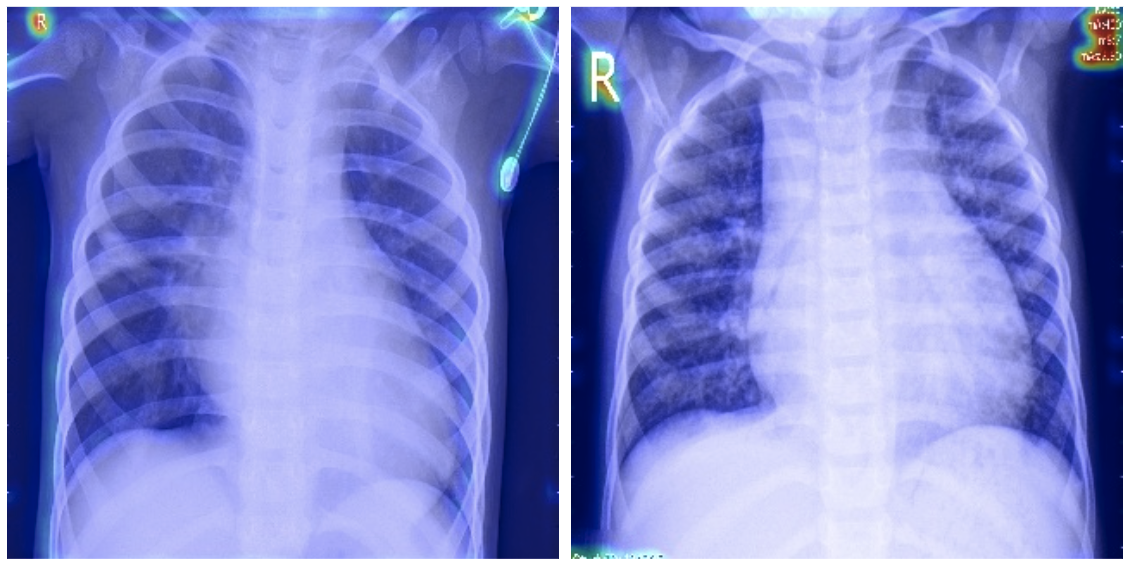

Grad-CAM is widely applicable across industries that rely on deep learning for image-based tasks. In healthcare, it can be used to explain predictions made by medical imaging models. For instance, a Grad-CAM heatmap applied to a pneumonia detection model can confirm whether the model is focusing on the correct regions of an X-ray image. This level of transparency is critical for building trust with medical professionals and ensuring accurate diagnoses. See below for an example where a dataset used for a pneumonia detector contain biases.

On medical imagery, often images are being annotated or contains a scale. Below in another example of a model focusing on the annotations instead of the actual region of interest.